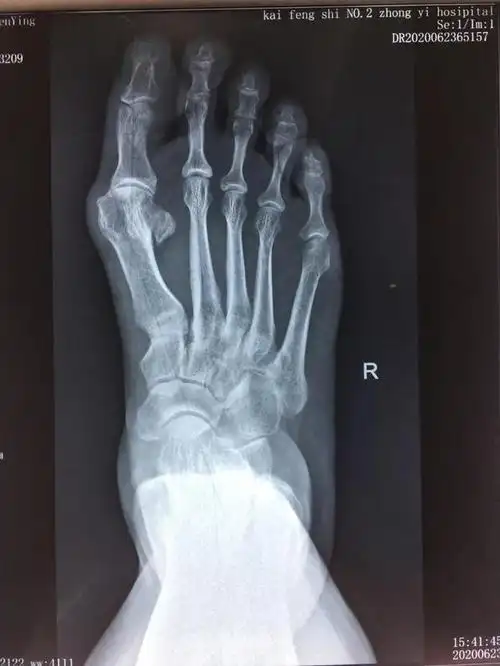

负重x线片观察:第一二跖骨间夹角增大明显,第二跖趾关节半脱位.